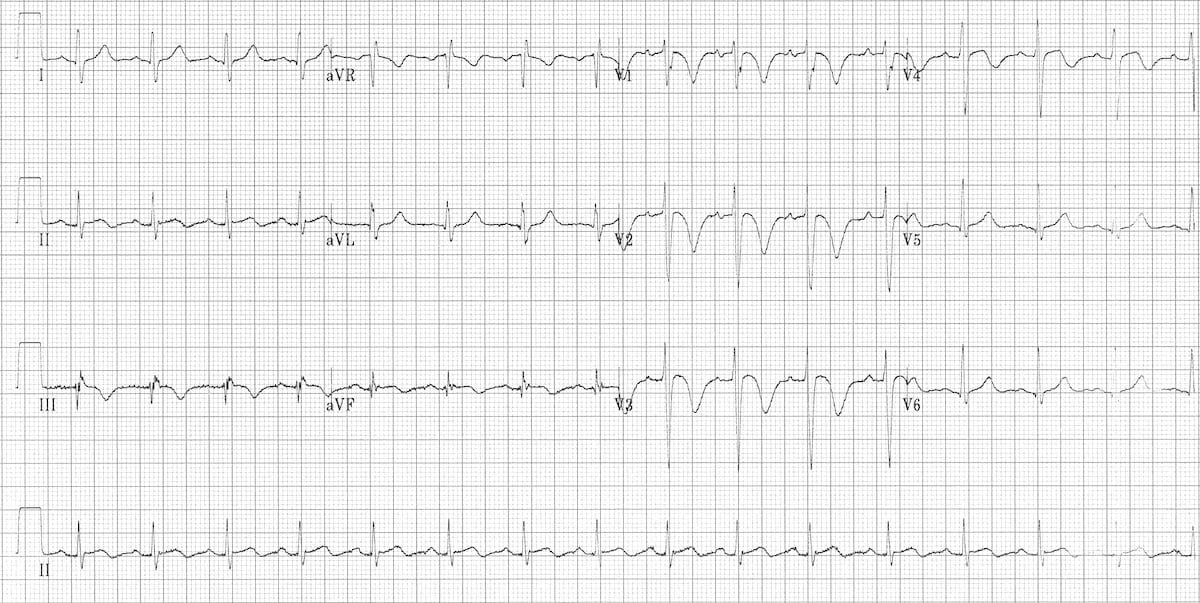

This ECG shows features suggestive of PE. Sinus tachycardia is present (rate 100 bpm). There is clear T wave inversion in right precordial leads (V1-V4) and in inferior leads (II, III, aVF). S1Q3T3 pattern is also present.

https://litfl.com/pulmonary-embolism-ecg-library/

© Life in the Fast Lane. Licensed under CC BY-NC 4.0